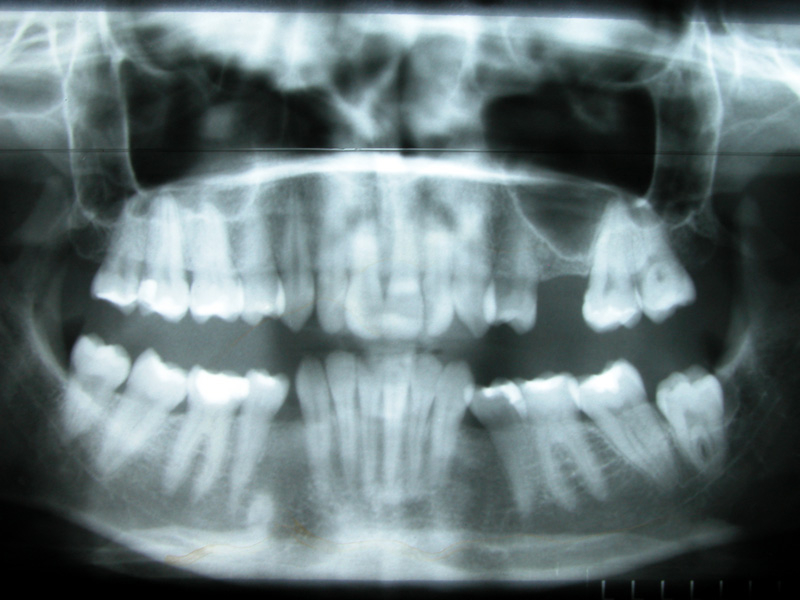

Implante - Galerie Foto

Caz I